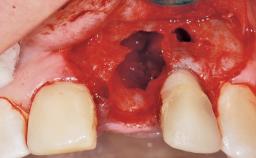

A 30-year-old female patient was referred to the office for the treatment of tooth 11. Her chief concern at the initial visit was to inquire, “Why is my tooth pink?” Upon clinical examination, it was determined that tooth 11 had a previous history of trauma and that the clinical crown had become noticeably pink in color as a result of internal resorption. This diagnosis was confirmed radiographically, indicating a large radiolucency involving the central and distal portions of the clinical crown. It was determined that restoration of this tooth was not possible, and that extraction was indicated. The presence of a mid-line diastema, which the patient wanted to reproduce, directed the treatment plan for tooth replacement utilizing a dental implant.

Bone Augmentation Horizontal|Simultaneous

Augmentation Materials Autogenous chips|Membrane

Placement Protocol Immediate implant placement

Socket Integrity Sufficient, with intact bone walls

Bone Volume Sufficient, with intact walls